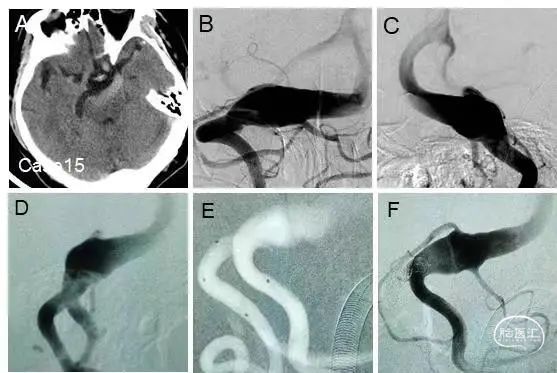

病例15

椎基底动脉冗长扩张症的一期治疗

1-2个月后来院二期处理